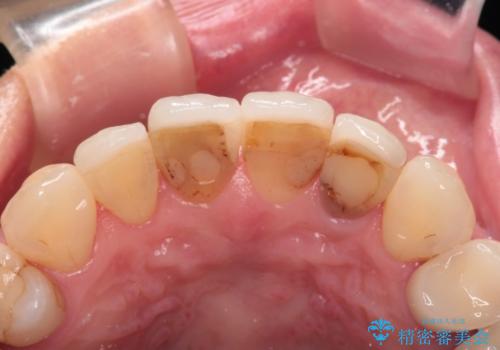

- 他院で治療したラミネートベニアをきれいにやり替えたいと来院された患者様です。

ラミネートベニアの欠けてしまっているところをコンポジットレジンで修復してあり、変色が目立ちます。

また、ラミネートベニアと歯茎の境目も気になります。

根管治療をしている歯もあるため、オールセラミッククラウンにすることとしました。

再根管治療は希望されなかったため、土台のやり替えから行いました。